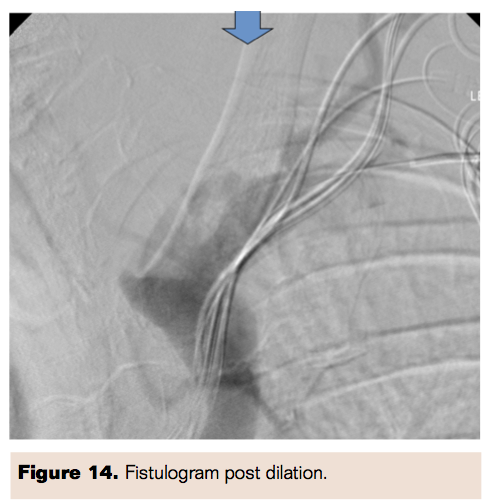

A 73-year-old male with stage 4 chronic kidney disease had previously received a brachiobasilic AVF. On follow-up, he was noted to have a persistent massively swollen left arm. An initial fistulogram demonstrated central venous outflow stenosis (Figure 12). Angioplasty was performed on the lesion (Figure 13) and a post dilation fistulogram demonstrated resolution in the outlet obstruction stenosis (Figure 14).